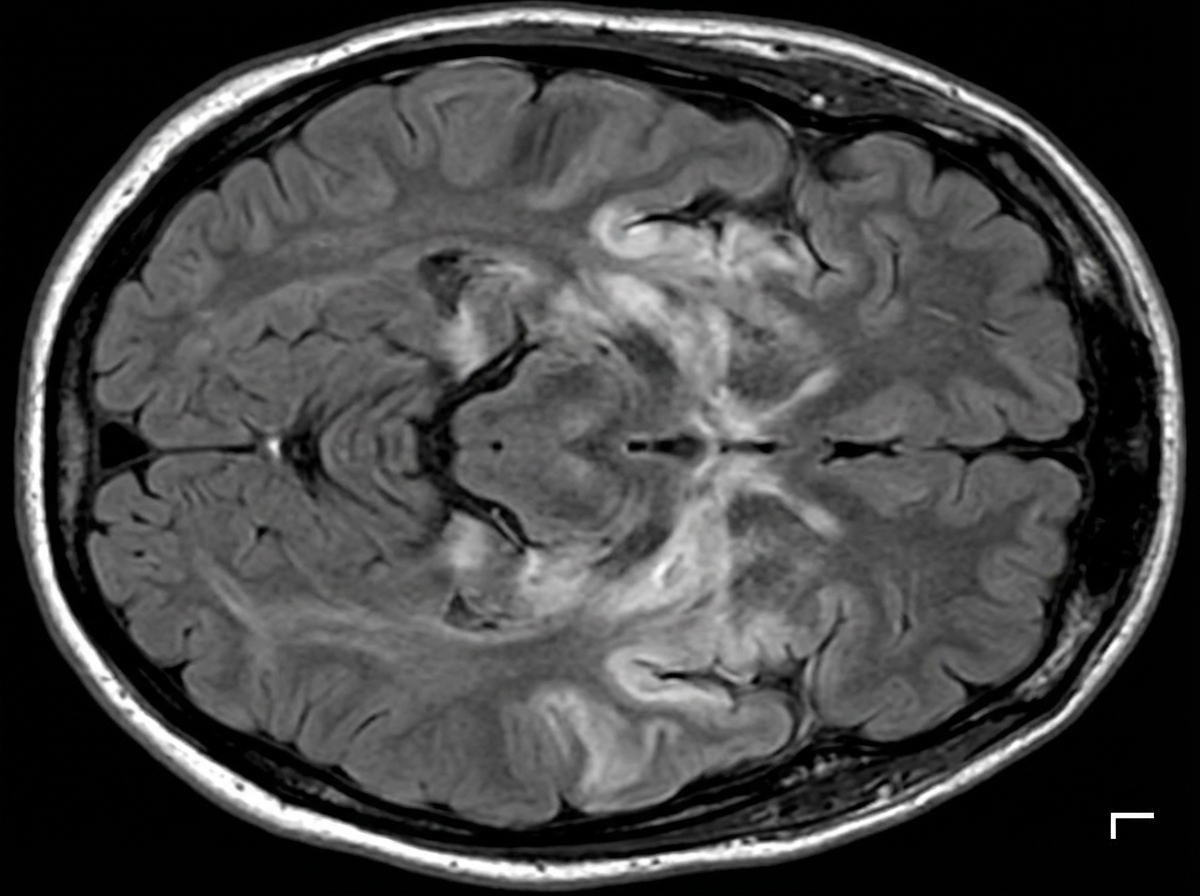

A 27-year-old man is brought to the emergency department by his friends in a confused state. He was doing fine 5 days ago when he started to complain of fever and flu-like symptoms. His fever was low-grade and associated with a headache. For the past 2 days, he has become increasingly irritable, confused, and was getting angry at trivial things. Past medical history is unremarkable. He is a college student and is physically active. He smokes cigarettes occasionally. He drinks alcohol socially. He is sexually active with his girlfriend and they use condoms inconsistently. Physical examination reveals: blood pressure 120/80 mm Hg, heart rate 108/min, respiratory rate 10/min, and temperature 37.4°C (99.4°F). He is confused and disoriented. Pupils are 3 mm in diameter and respond to light sluggishly. He is moving all his limbs spontaneously. His neck is supple. MRI of the brain is shown in the picture. Cerebrospinal fluid (CSF) reveals an opening pressure of 16 cm of H20, a total leukocyte count of 112/mm3 with 85% lymphocytes, the protein of 42 mg/dL, and glucose of 58 mg/dL. What is the best treatment for this condition?

Explanation: ***Acyclovir*** - The patient's presentation with **fever**, **flu-like symptoms** followed by **irritability**, **confusion**, and **MRI findings** suggestive of temporal lobe involvement, along with **lymphocytic pleocytosis** in CSF, is highly indicative of **herpes simplex encephalitis (HSE)**. - **Acyclovir** is the treatment of choice for HSE, as it is an antiviral drug effective against the **herpes simplex virus (HSV)**. Prompt administration significantly improves outcomes. *Intravenous immunoglobulin* - **Intravenous immunoglobulin (IVIG)** is generally used for certain **immunodeficiencies** or **autoimmune conditions**, not for acute viral encephalitis like HSE. - There is no evidence to support the use of IVIG as a primary treatment for HSV encephalitis. *High-dose steroids* - While steroids can reduce cerebral edema and inflammation, their routine use in **viral encephalitis** like HSE is **controversial** and not a first-line treatment. - Steroids might be considered in specific cases of severe cerebral edema, but not as the primary antiviral therapy. *Rituximab* - **Rituximab** is a **monoclonal antibody** targeting **CD20-positive B cells**, primarily used in certain **lymphomas** and **autoimmune diseases** like **rheumatoid arthritis** or **multiple sclerosis**. - It has no role in the treatment of acute viral encephalitis. *Ceftriaxone* - **Ceftriaxone** is a broad-spectrum **antibiotic** used to treat **bacterial meningitis** or other bacterial infections. - It is ineffective against viral infections such as HSV encephalitis.